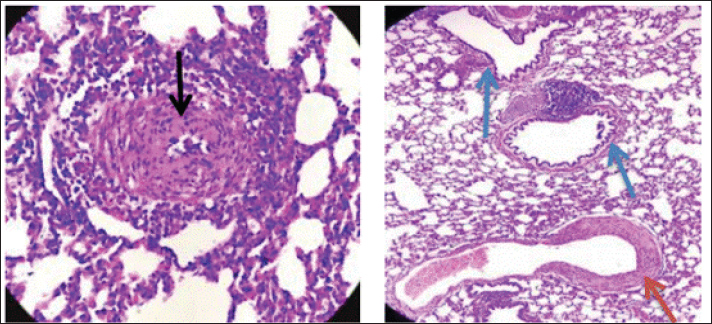

The short respiratory passage and direct bronchial branching in rabbits (Abdelsalam and Al Sadrani, 2015) likely contribute to higher lung infection rates. Additionally, the similarity between Raoultella and Klebsiella (Alampoondi Venkataramanan et al., 2021) complicates microscopic differentiation, necessitating advanced diagnostic methods like Vitek2.Contrary to Vinshia, J. J., (2024), this study found no fibrinous bronchopneumonia, instead emphasizing edema and congestion (Das and Bhagman, 1997). The reclassification of Raoultella from Klebsiella prior to 2001 further underscores the need for precise microbiological identification (Fig. 8). This study highlights Raoultella planticola's potential to cause respiratory pathology, warranting further investigation into its zoonotic risks.

Fig. 8. Group of infected rabbits show(A) arterioles moerate perivascular mononuclear cells infiltration with evidence of vasculitis (black arrow) H&E stain 400X. and B show tertiary bronchioles (blue arrow)with dilated pulmonary arterioles(red arrow) and the lung is show emphysema. H&E stain 100X.